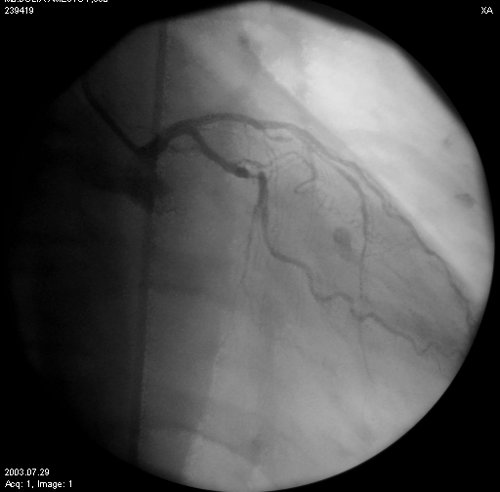

En control en policlínica al mes del evento, la paciente persiste con dolor torácico, por lo cual se realiza CACG a los 20 días del ingreso. El estudio mostró lesión en tandem de tercio medio de la arteria descendente anterior (ADA) y lesión severa proximal de arteria marginal obtusa (AMO), realizándose angioplastia exitosa en ambos vasos e implante de tres stents metálicos (fig. 3).